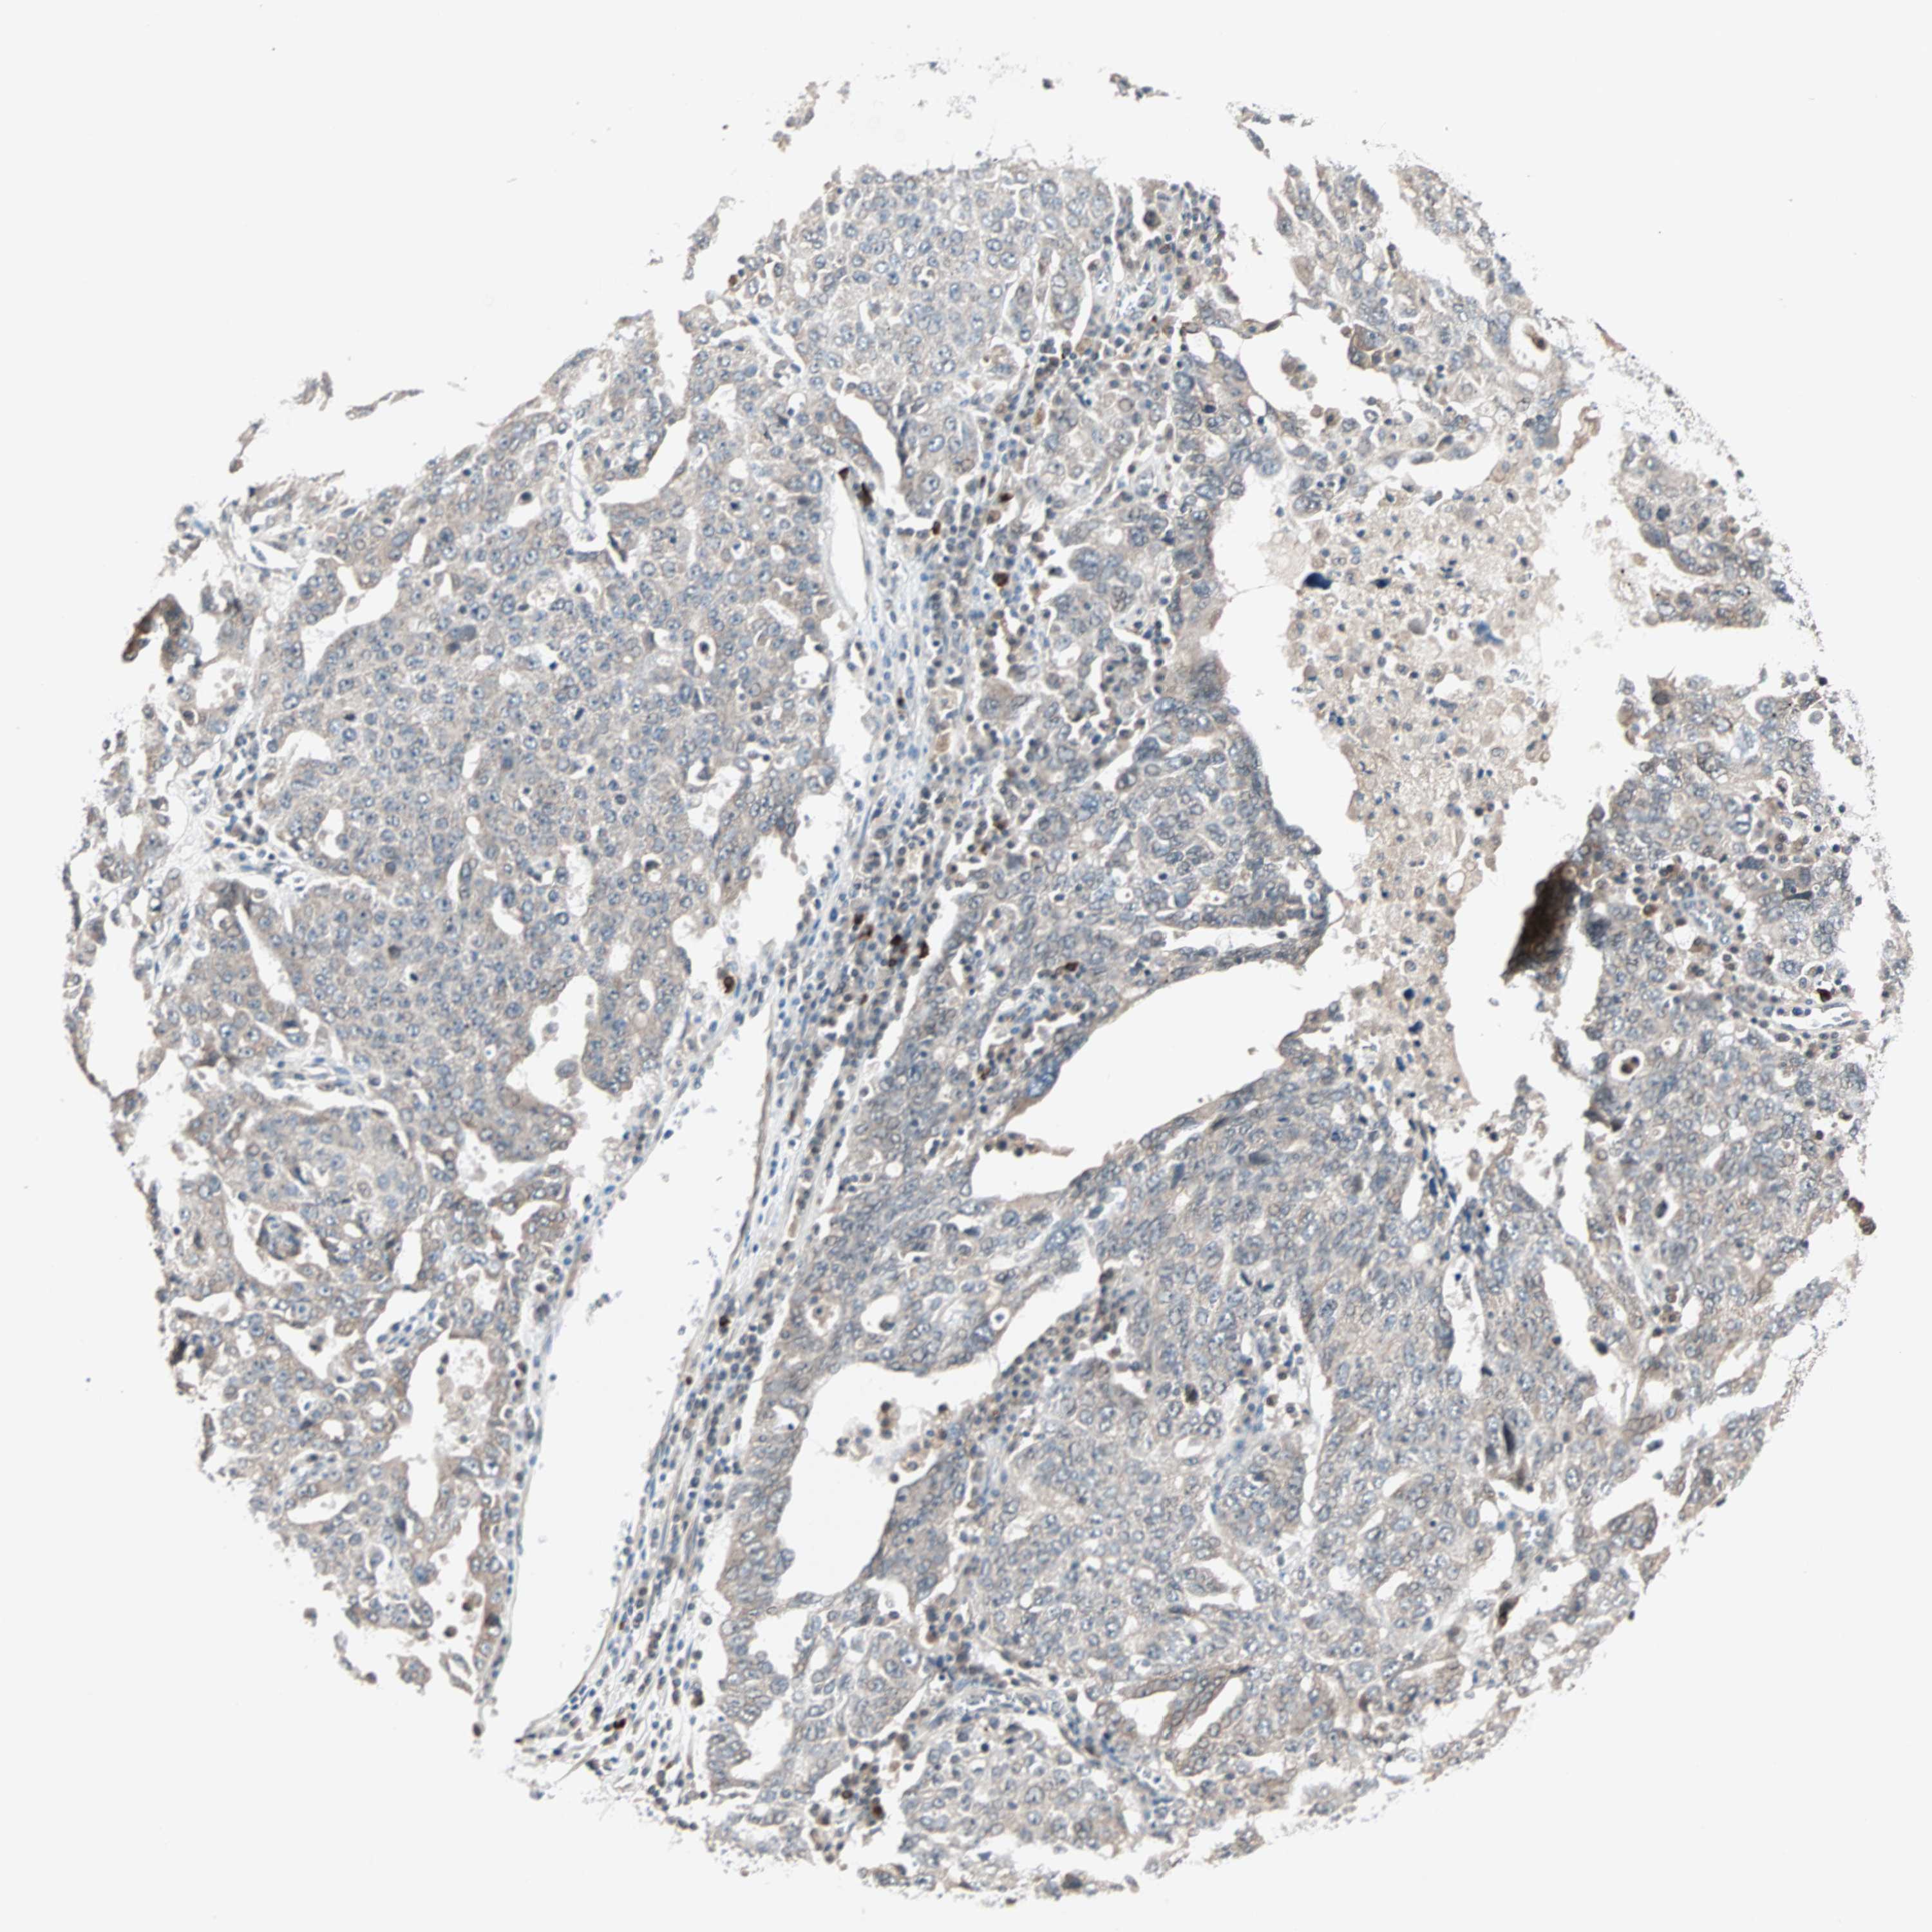

OVARIAN CANCER - Protein expressioni

A mouse-over function shows sample information and annotation data. Click on an image to view it in a full screen mode. Samples can be filtered based on level of antibody staining by selecting one or several of the following categories: high, medium, low and not detected. The assay and annotation is described here.

Note that samples used for immunohistochemistry by the Human Protein Atlas do not correspond to samples in the TCGA dataset.

Antibody stainingi

Antibody staining in the annotated cell types in the current human tissue is reported as not detected, low, medium, or high, based on conventional immunohistochemistry profiling in selected tissues. This score is based on the combination of the staining intensity and fraction of stained cells.

Each image is clickable and will lead to virtual microscopy that enables deeper exploration of all samples and also displays staining intensity scores, fraction scores and subcellular localization as well as patient and tissue information for each sample.

Antibody HPA007267

Staining

High

Medium

Low

Not detected

Intensity

Strong

Moderate

Weak

Negative

Quantity

>75%

75%-25%

<25%

None

Location

Nuclear

Cytoplasmic/membranous

Cytoplasmic/membranous,nuclear

Cystadenocarcinoma, serous, NOS

Carcinoma, endometroid

Cystadenocarcinoma, mucinous, NOS

Carcinoma, NOS